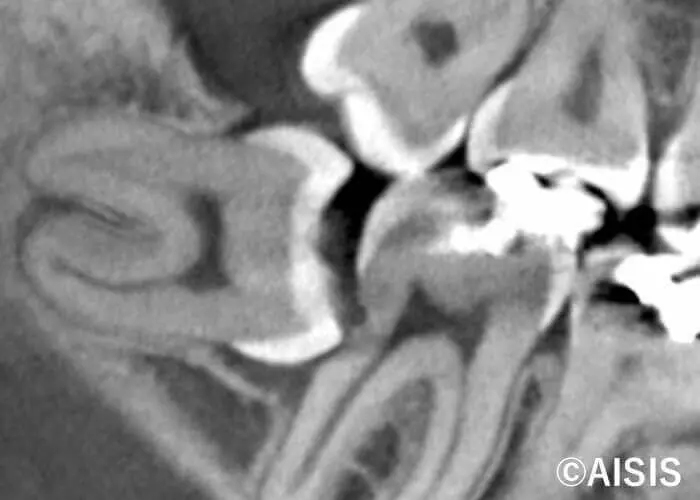

掲載しているレントゲン写真では、親知らずが横向きに生えており、手前の歯と接している部分が黒く写っているのが確認できます。この黒く見える部分は、実際に虫歯が進行している箇所です。

王寺町の歯医者 王寺FIVEおとなこども歯科では、必要に応じてCT撮影を行い、親知らずの位置や神経との距離、骨の状態などを事前に詳しく確認した上で抜歯を行います。また、マイクロスコープを用いた高精度な治療により、安全性と精密性に配慮した抜歯を行っておりますので、親知らずでお悩みの方はお気軽にご相談ください。